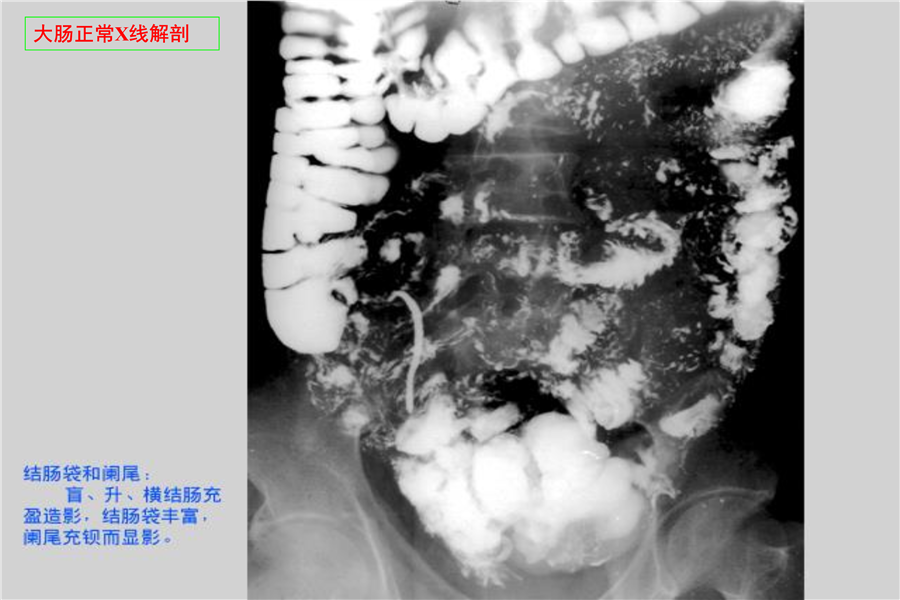

消化系统一